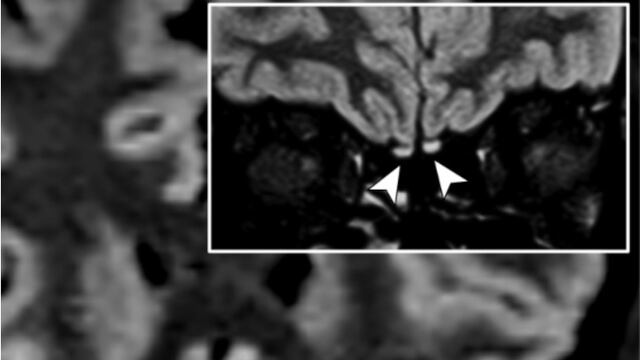

En imágenes tridimensionales y bidimensionales de recuperación de inversión atenuada por líquido, se evidenció una hiperintensidad cortical en el giro recto derecho y una hiperintensidad sutil en los bulbos olfatorios.

En consecuencia, durante una resonancia magnética de seguimiento realizada 28 días después, la alteración de la señal en la corteza desapareció por completo y los bulbos olfatorios eran más delgados y un poco menos hiperintensos. Por ende, la mujer se recuperó de la anosmia y no se observaron anomalías cerebrales.